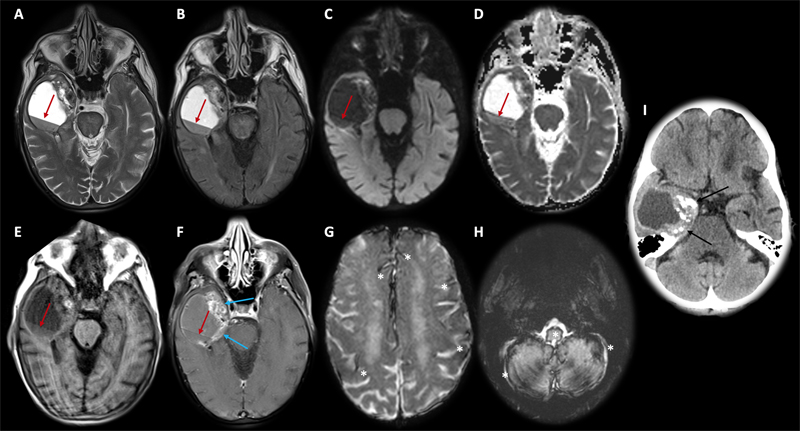

A 66-year-old female with a history of smoking and localized squamous cell carcinoma of the right nare diagnosed 4 years prior presented to the emergency room with one week of confusion and falls, which had worsened in the last day. Brain imaging revealed a heterogeneously enhancing right anterior temporal lobe mass with solid and cystic components. There was evidence of hemorrhage within the tumor and in the subarachnoid space, as well as supra- and infratentorial superficial siderosis (Figure 1). The patient underwent gross total tumor resection and recovered well after the surgery.

Figure 1. Axial brain MRI (A–H) and CT (I) images. Large right temporal solid and cystic lesion with blood level (red arrows) and heterogeneous contrast enhancement in the medial margin (blue arrows). There was no restricted diffusion (C and D). T2* magnetic susceptibility sequence (G and H) showed extensive supra- and infratentorial superficial siderosis (white asterisks). Multiple punctate calcifications along the solid tumoral medial margin are seen on CT imaging (I, black arrows).